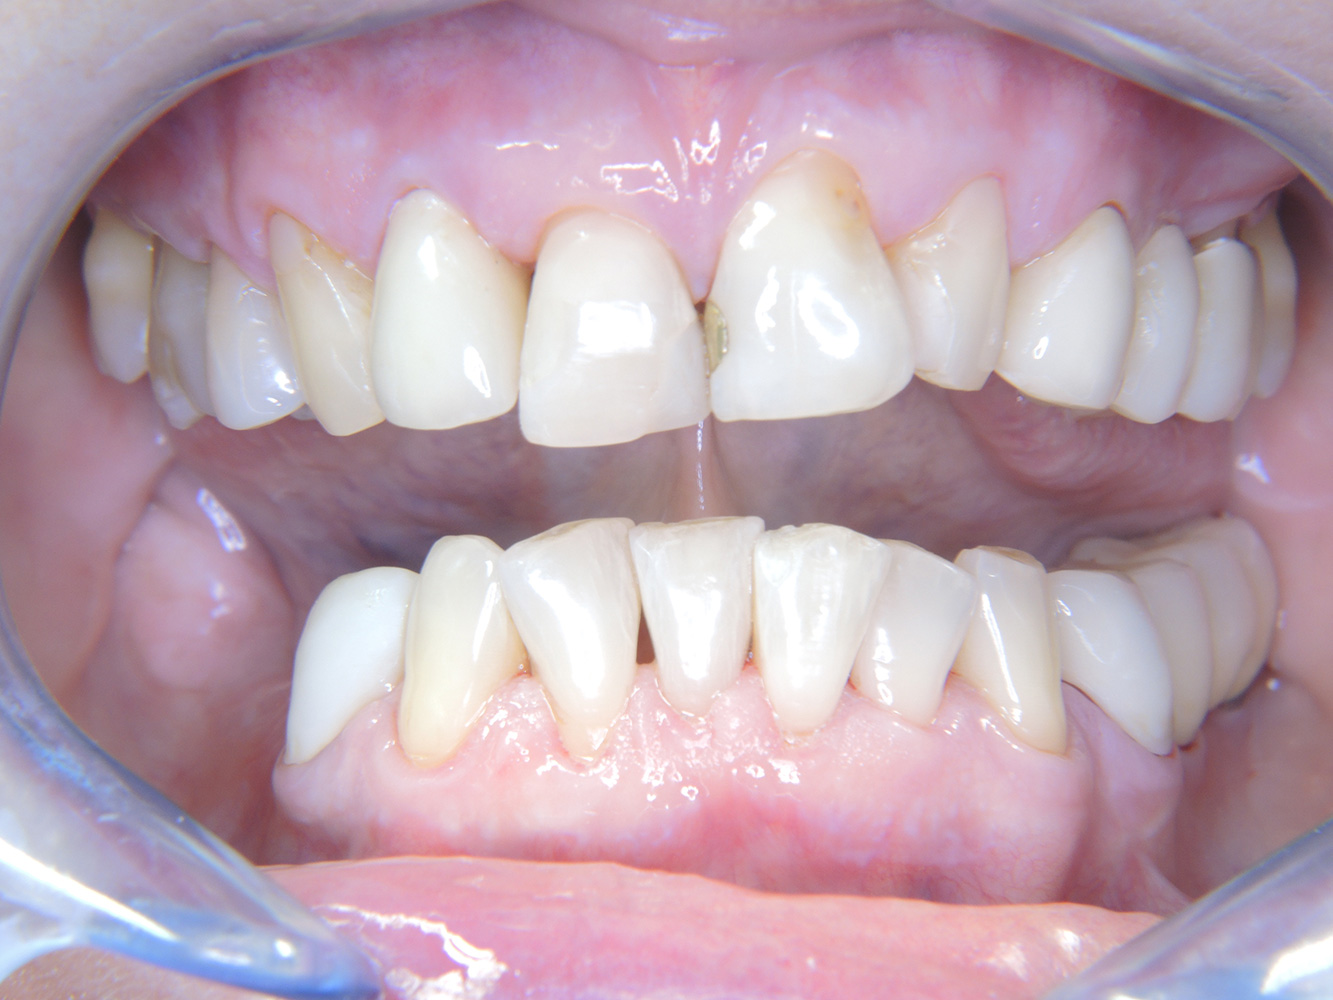

Paciente sana con enfermedad periodontal previa*

La paciente de 68 años no tiene enfermedades previas relevantes de la salud general ni toma medicación; sus hábitos alimentarios tampoco suponen un riesgo especial. La paciente tiene dos implantes (tercer cuadrante, desde hace cinco años) y una enfermedad previa periodontal (periodontitis en etapa IV, grado B) con pérdida dental. Actualmente las condiciones periodontales son estables, pero la periodontitis aumenta de manera determinante las complicaciones biológicas cuando se realizan implantes y puede ocasionar la pérdida de un implante (21). Para la sesión de profilaxis se hacen cuatro recomendaciones.